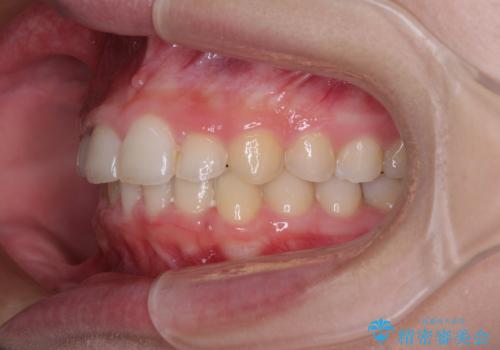

- 前歯の歯並びと不自然な色をした前歯のクラウンを気にして来院された患者様です。

上下前歯の歯列不正はインビザラインにより歯列を整え、その後に、前歯をオーダーメイドタイプのオールセラミッククラウンにて補綴治療することとしました。

前歯のデコボコを一番気にしていらっしゃいましたが、矯正治療により下顎前歯が隠れるほどのディープバイトも一緒に改善され、奥歯に負担のかかりにくい咬み合わせとなりました。